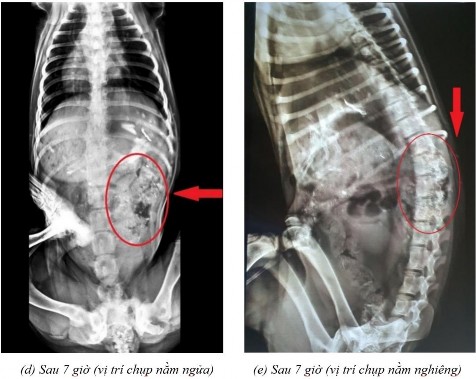

Phụ lục 5.4. Hình ảnh X-quang chó 5 ở thời điểm (a) sau 2 giờ 20 ở vị trí nằm nghiêng, (b) sau 4 giờ ở vị trí nằm ngửa, (c) sau 4 giờ ở vị trí nằm nghiêng, (d) sau 7 giờ ở vị trí nằm ngửa, (e) sau 7 giờ ở vị trí nằm nghiêng, (f) sau 9 giờ ở vị trí nằm ngửa, (g) sau 9 giờ ở vị trí nằm nghiêng, (h) sau 11 giờ 40 ở vị trí nằm ngửa và (i) sau 11 giờ 40 ở vị trí nằm nghiêng